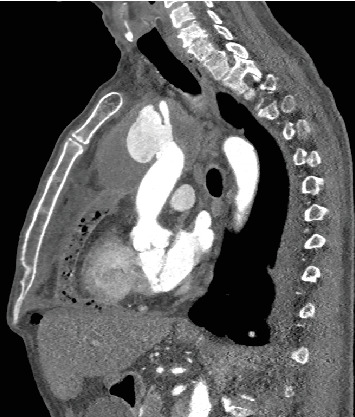

An infection and aortic arch pseudoaneurysm can be fatal if not emergently and adequately treated. Optimal surgical procedures and optimal graft materials remain controversial. We describe a 61-year-old patient who underwent in situ repair of the infected pseudoaneurysm of the aortic arch. A porcine pericardium patch (BioIntegral Surgical Inc., Mississauga, ON, Canada) was used to reconstruct the aortic wall, followed by the reconstruction of the brachiocephalic trunk using a surgeon-made tube. The patient made a full recovery. Self-made tube grafts for in situ reconstruction offer many advantages and may be a valuable option.

Abstract Image